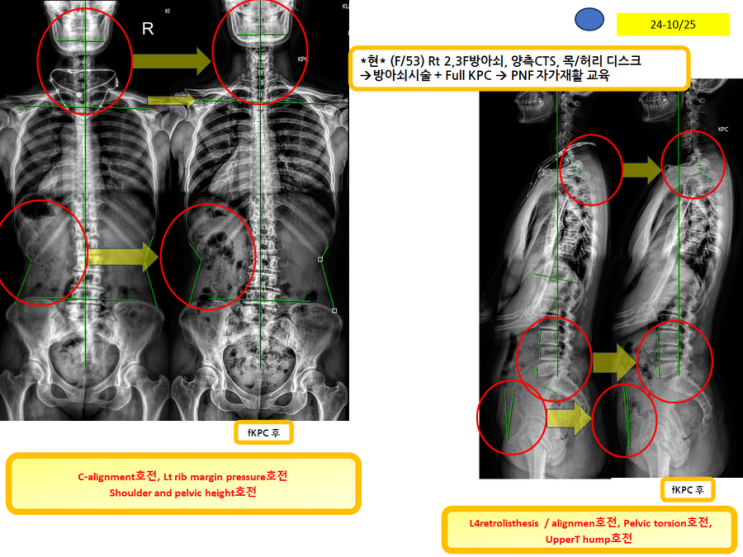

방아쇠시술하러오셨는데 목,허리 디스크 등으로 고생했던 분!(녹는실KPC치료는 엑스레이 호전을 10분만에 확인)

방아쇠시술하러오셨는데 목,허리 디스크 등으로 고생했던 분! (녹는실KPC치료는 엑스레이 호전을 10분만...